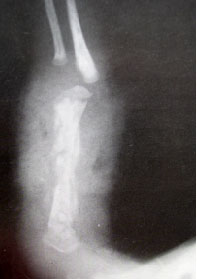

x光片报告单,x光片胸片

念珠菌性骨髓炎

x光片骨折